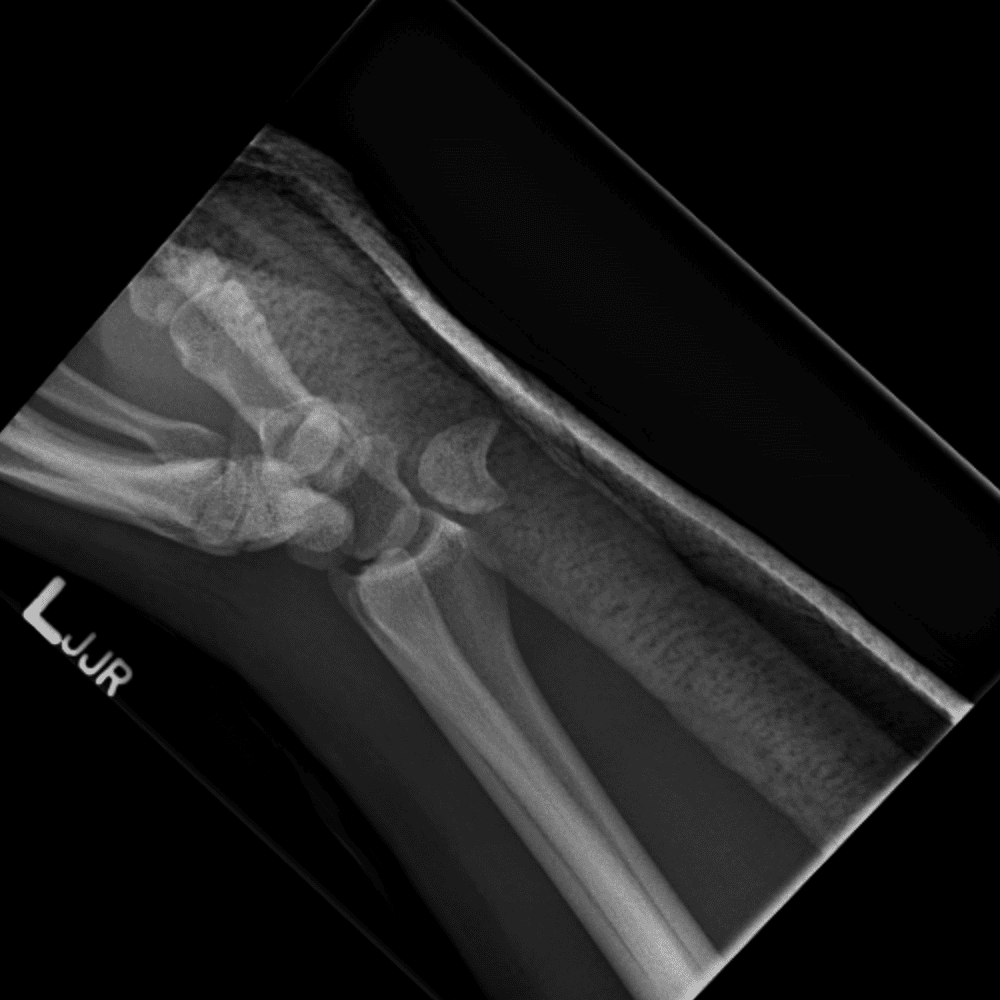

Simulates call by including subtle or difficult cases and some normals.

30 cases